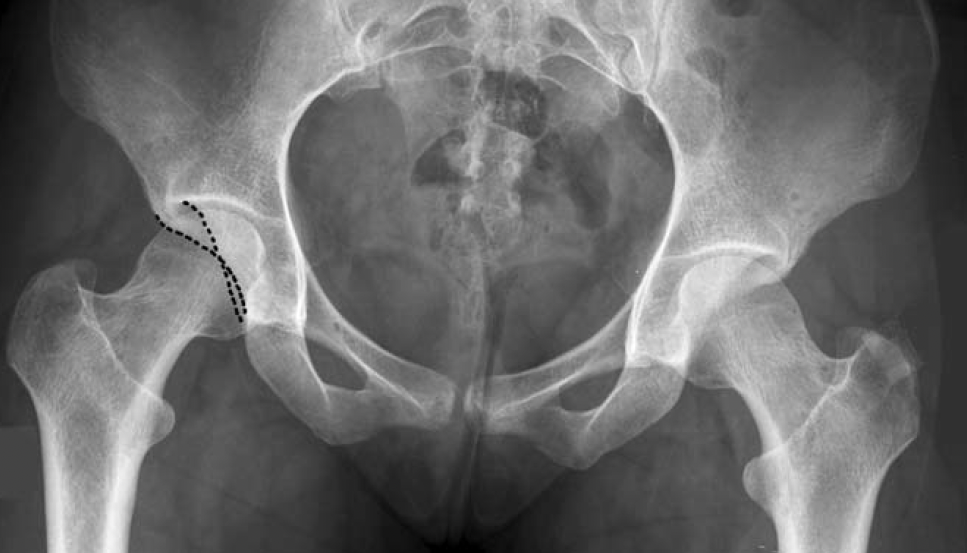

Anatomisch werden drei Hauptformen unterschieden: das Cam-Impingement, bei dem der Übergang zwischen Kopf und Schaft des Femurs abgeflacht ist, das Pincer-Impingement, bei dem der Pfannenrand übermäßig ausgeprägt ist (Anzillotti et al., 2022). Die dritte ist eine häufig vorliegende Mischform. Risikofaktoren für ein Hüftimpingement sind sportliche Aktivitäten mit intensiver Hüftbeugung und -rotation (z. B. Fußball, Kampfsport, Turnen) sowie genetische Einflüsse (Frank et al., 2015).

- Der Cam-Typ ist gekennzeichnet durch einen abnorm geformten Oberschenkelknochenkopf, der sich beim Bewegen in die Hüftpfanne einbohrt

- Beim Pincer-Typ überdeckt die Hüftpfanne den Oberschenkelknochen zu weit und führt ebenfalls zu Reibung und Schmerzen